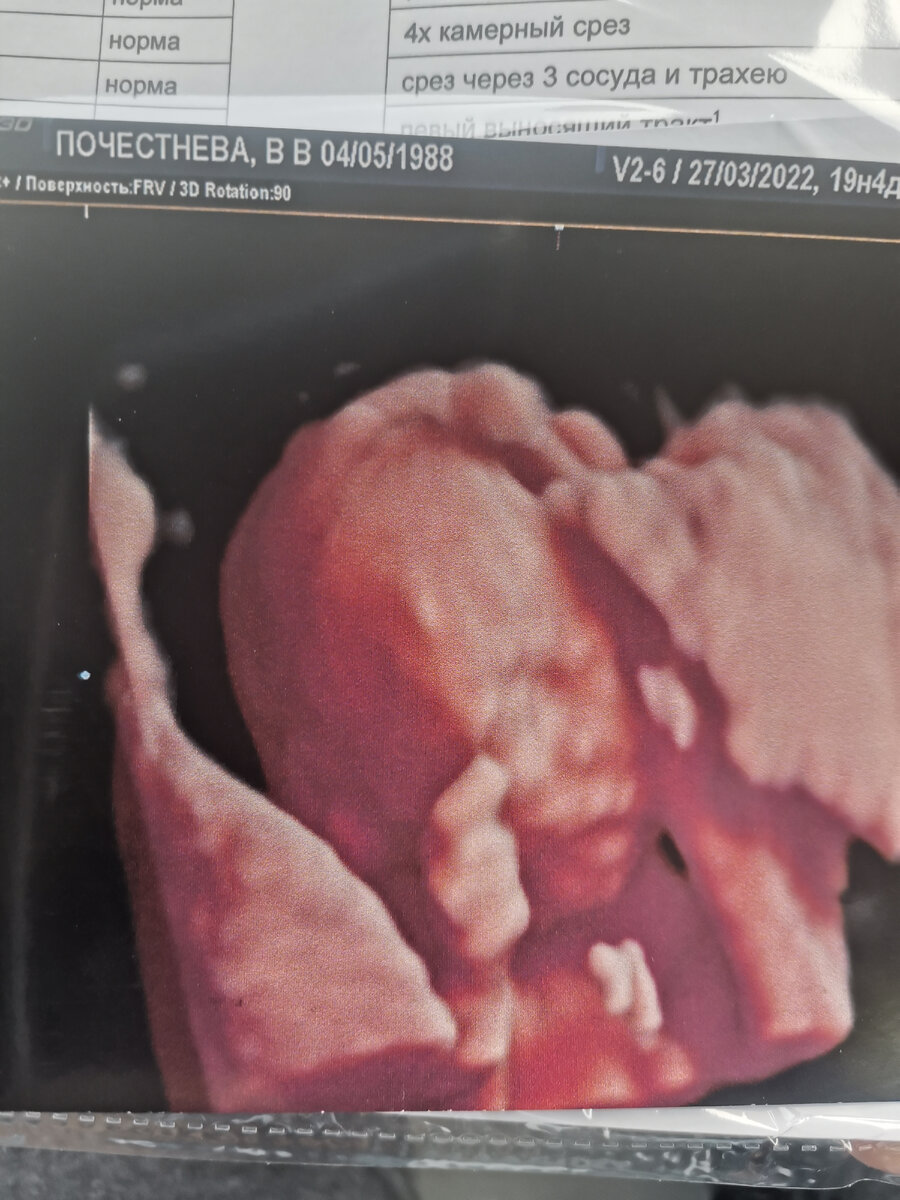

А через две недели на 21 мая мне назначили новое УЗИ, на котором мы уже увидели нашего малыша, крохотуличку. Услышали как бьётся его маленькое сердечко❤️

А на втором УЗИ нам сказали пол малыша. Папа был уверен что дочь,а вот я знала, чувствовала что в этот раз ношу сына.

Так и случилось, врач спросил знаем ли мы пол и хотели бы узнать сейчас!?)

Потом потомил, потянул с ожиданием минуту-другую, которая показалась нам вечностью и в итоге сказал:поздравляю вас! У вас самый что ни на есть настоящий мальчик❤️❤️❤️

Вот такой вот. Настоящий сын.)